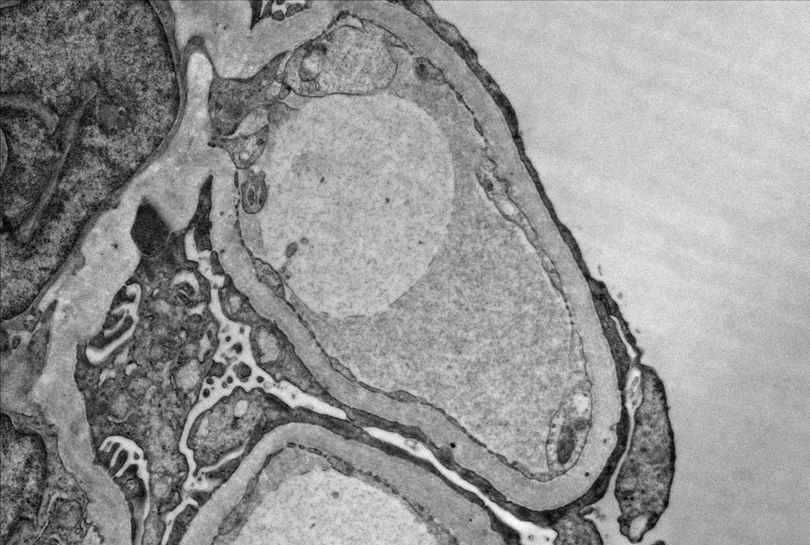

How about our patient with COVID-19 and nephrotic syndrome? The biopsy reveals collapsing FSGS!

Above, we see collapse of the capillary loops along with hypertrophy and hyperplasia of the podocytes. We also see effaced podocytes under electron microscopy (EM). Viruses have been commonly associated with collapsing FSGS or collapsing glomerulopathy (think: human immunodeficiency virus (HIV), cytomegalovirus (CMV), parvovirus B19) – and seem SARS-CoV2 has been added to the list: meet COVAN (COVID-19 associated nephropathy). Collapsing glomerulopathy has been reported in individuals of African ancestry with COVID-19 and high-risk apolipoprotein 1 (APOL1) alleles. A proposed pathogenesis of COVAN is summarized in the figure below.